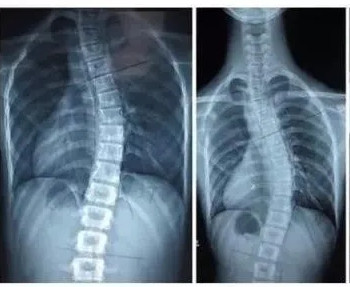

脊柱側(cè)彎是一種脊柱的三維畸形,在失狀面,冠狀面,橫斷面上的序列均會(huì)產(chǎn)生異常。在X光檢查中如果顯示脊柱有10度以上的側(cè)方彎曲,即會(huì)診斷為脊柱側(cè)彎。